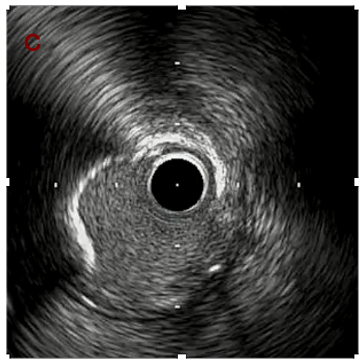

IVUS after OAS high speed 3回追加

IVUS imaging after high speed 3回追加

a,b,cの十分な石灰化のsanding。

High riskのbias所見へと変わっていったdの部位に関してはpinpoint OASを行うことでinjuryなく治療できた。

Cutting + DCBの方針に。